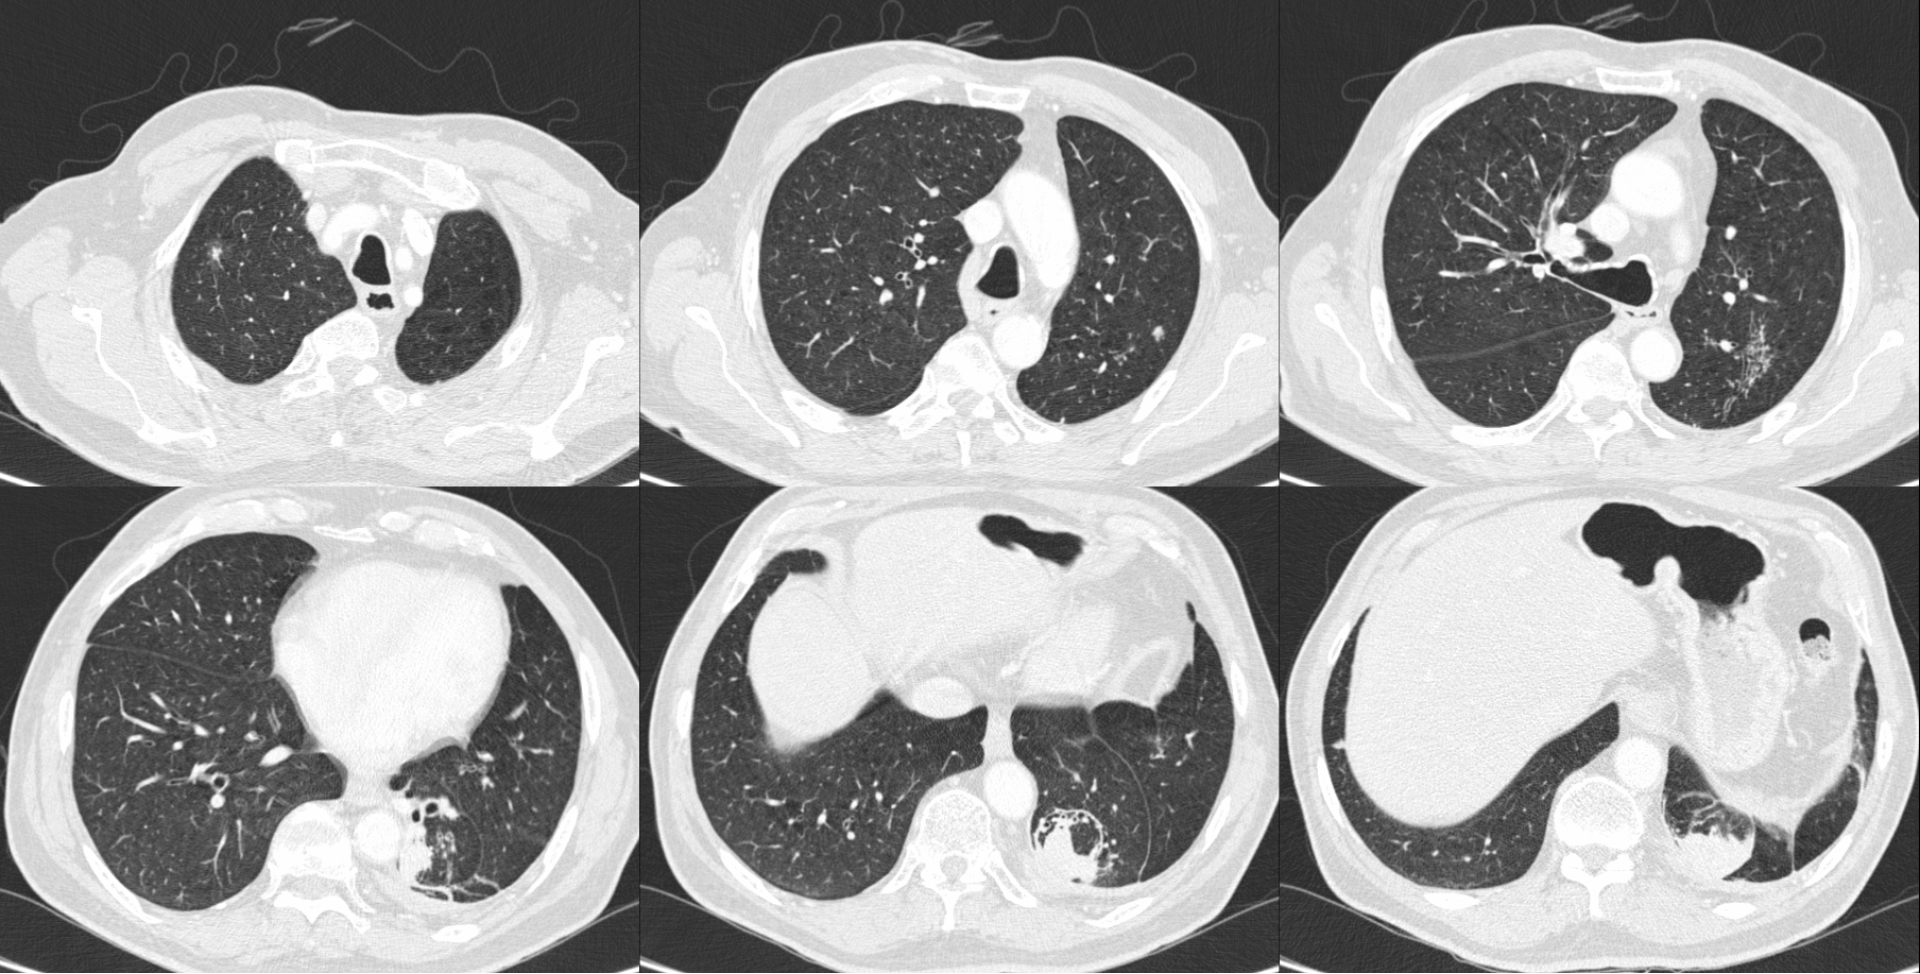

Case 113: Round with a Comet Tail

A 74-years old man with a 21 pack years history of smoking presented with fever and weight loss

There are multiple findings in these images. However, he was diagnosed to have a left lower lobe pneumonia.

The video discusses the case and all the terminologies associated with a diagnosis of a fungal ball in a cavity